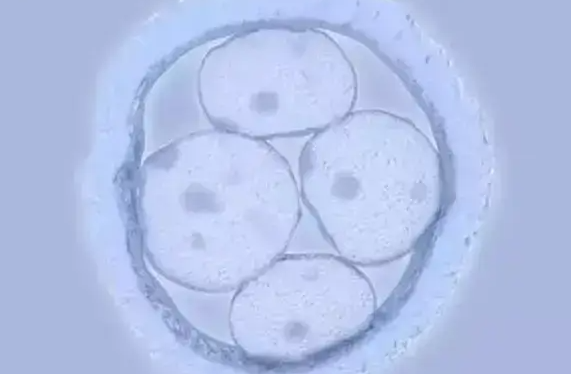

美国EFC生殖中心三代试管婴儿:胚胎级别与成功率的深度解析